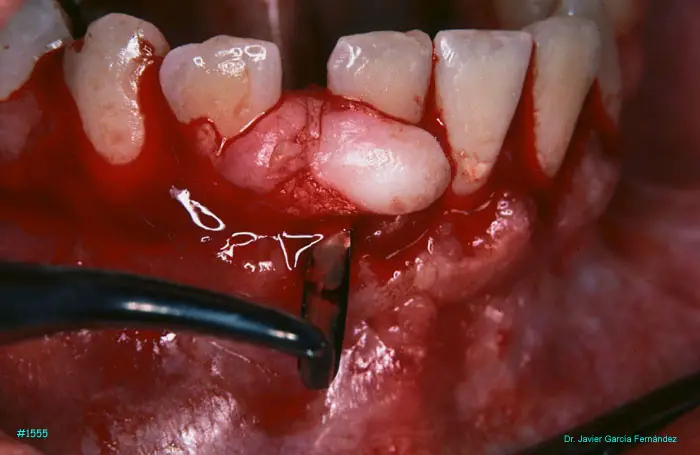

Atlas of Surgical Techniques in Periodontics. Chapter IV. Atlas de Técnicas Quirúrgica en Periodoncia

image 081